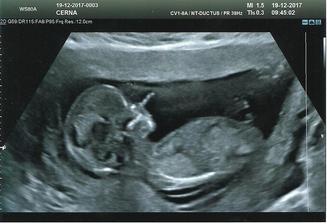

Kouzlo lásky=o)

naše druhé štěstí